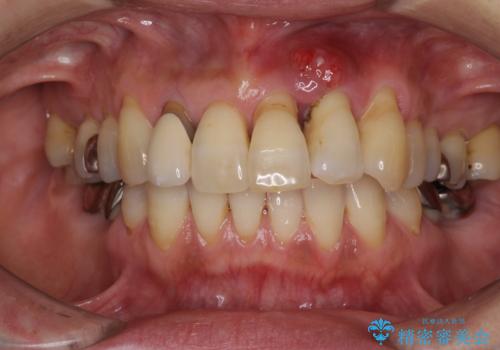

[ セラミック・インプラント全顎治療 ] 長年悩まされている歯の治療にケリをつけたい

![[ セラミック・インプラント全顎治療 ] 長年悩まされている歯の治療にケリをつけたいの症例 治療前](https://seimitsushinbi.jp/wp/wp-content/uploads/2022/01/699ba08b6e311b07f9d2ea9a5b757aea-500x350.jpg?v=1642042101)